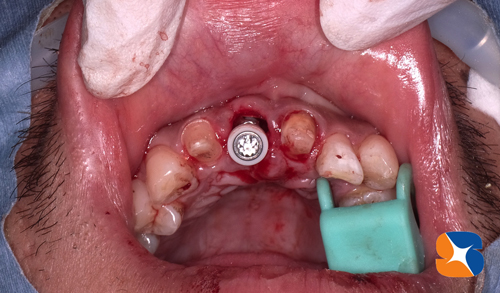

82歳の女性。主訴は「前歯がグラついて抜けそう。歯茎に突起物も頻繁に出来る。いよいよ抜歯かな?でも入れ歯だけは絶対イヤ!」でした。

CTを使用して歯根の周囲骨の欠落状態をチェックしたところ、グラつく前歯2本に、大きく骨の欠落を確認しました。歯根のひび割れ(1本または2本とも)が予測されたので、やはり抜歯の可能性がある事を伝えました。入れ歯を好まない患者様でしたので、1本または2本のインプラント治療をされることに決まりました。

手術前にまず、麻酔鎮静法(無料)を行い、うとうと眠った状態にします。点滴のお薬が効いてくると、通常の麻酔と同時に採血も行います。当院は即時に細胞(フィブリノーゲン)を培養する施設の認可を取っていますので、その場で出来上がったCGFとAFG(無料)を骨の欠落している箇所に補填します。

もう1本のグラつきは、差し歯の外れかけが原因では?と予測していましたが、歯の根面に亀裂が入っている事を手術で確認しました。

左の写真は、抜歯したその日にインプラントを埋めたところです。同様に隣りのひび割れした歯も「抜歯→インプラント埋め」をその日のうちに行います。

※患者様には、事前に説明済み。

2本のインプラントが無事に埋められた後、動物由来ではない人工の骨と自己採血で製作された無添加自己フィブリンを混ぜ合わせ、グミ状に仕上げた混合物を、骨が不足している部分にたっぷり養生しました(写真=左)。

手術から僅か11日後の状態です。傷口も綺麗にふさがり、弾力に富んだ歯肉をしています。経過、良好です。